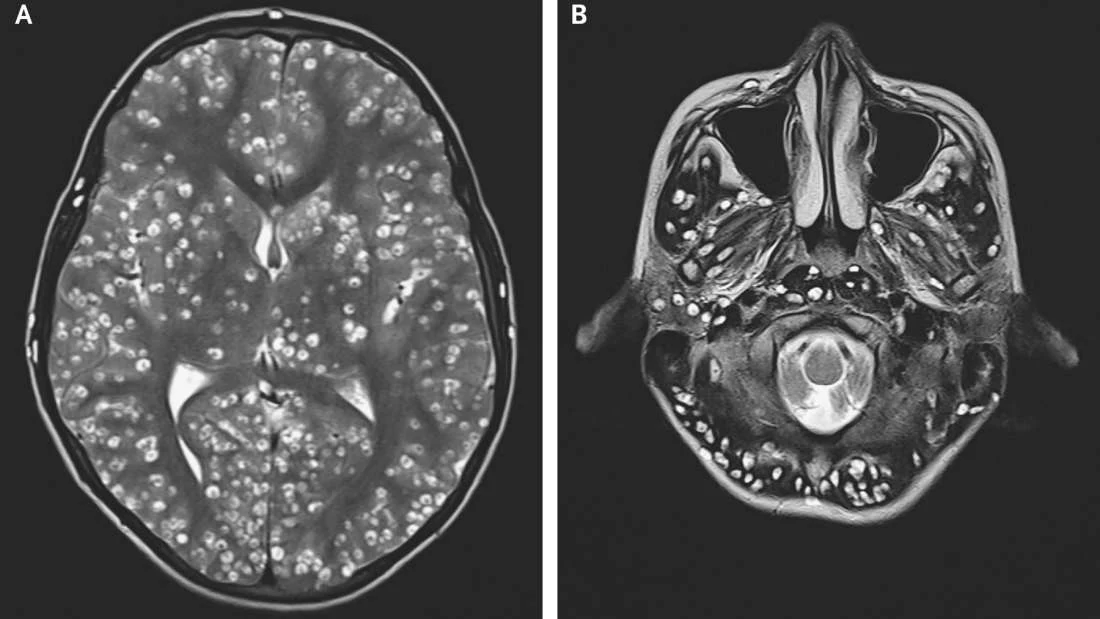

W "The New England Journal of Medicine" lekarze z Indii opisali ciekawy przypadek 18-letniego mężczyzny, który trafił do szpitala po serii napadów padaczkowych. Był on także zdezorientowany i cierpiał na obrzęk oka oraz tkliwość w prawym jądrze.Badanie za pomocą magnetycznego rezonansu jądrowego głowy wykazało obecność licznych zmian torbielowatych w zewnętrznej warstwie mózgu. Badania krwi potwierdziły później, że te objawy były wynikiem neurocysticerkozy, zakażenia tkanek spowodowanego larwami tasiemców Taenia solium.- Zarażenie zwykle występuje po spożyciu jaj tasiemca. Ich źródłem może być pokarm lub woda zanieczyszczona odchodami. Innym źródłem może być spożycie surowej wieprzowiny. Ponieważ pacjent był wegetarianinem, odrzuciliśmy tę trzecią opcję - powiedział dr Nishanth Dev, jeden z lekarzy badających ten przypadek.WHO zauważa, że infekcje związane z zakażeniem jajami tasiemców występują głównie w rozwijających się krajach Afryki, Azji i Ameryki Łacińskiej. W tych częściach świata neurocysticerkoza może stanowić prawie 1/3 wszystkich przypadków napadów padaczkowych.Co ciekawe, aż 2,5 do ponad 8 mln osób może cierpieć z powodu zarażenia larwami tasiemca i neurocysticerkozy, chociaż wielu lekarzy nie jest w stanie tego zdiagnozować. Opisany przypadek jest szczególnie ekstremalny.Niestety, podjęte leczenie okazało się nieskuteczne. Pomimo prób ratowania życia 18-latka, zmarł on w szpitalu dwa tygodnie później.